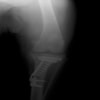

術前写真

手術前後のTPA(脛骨高平部の角度)を測定しています。

約29°から約10°へ矯正されています。